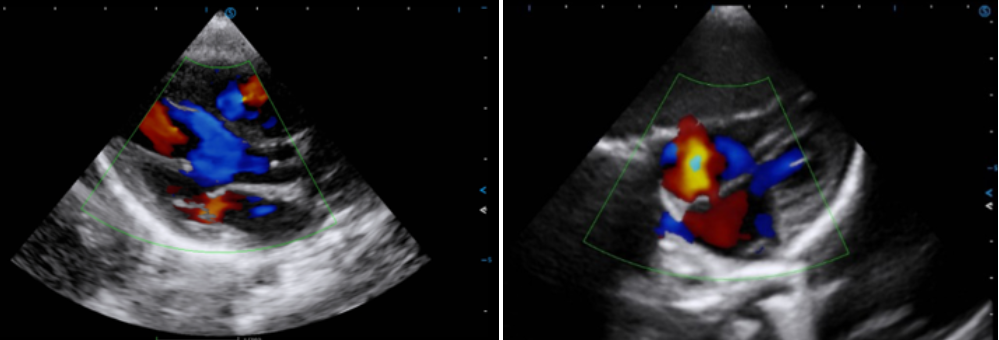

VS Flow is highly sensitive to low velocity blood flow signal and especially suitable for superficial blood flow examination

Click on images to enlarge

Click on images to enlarge